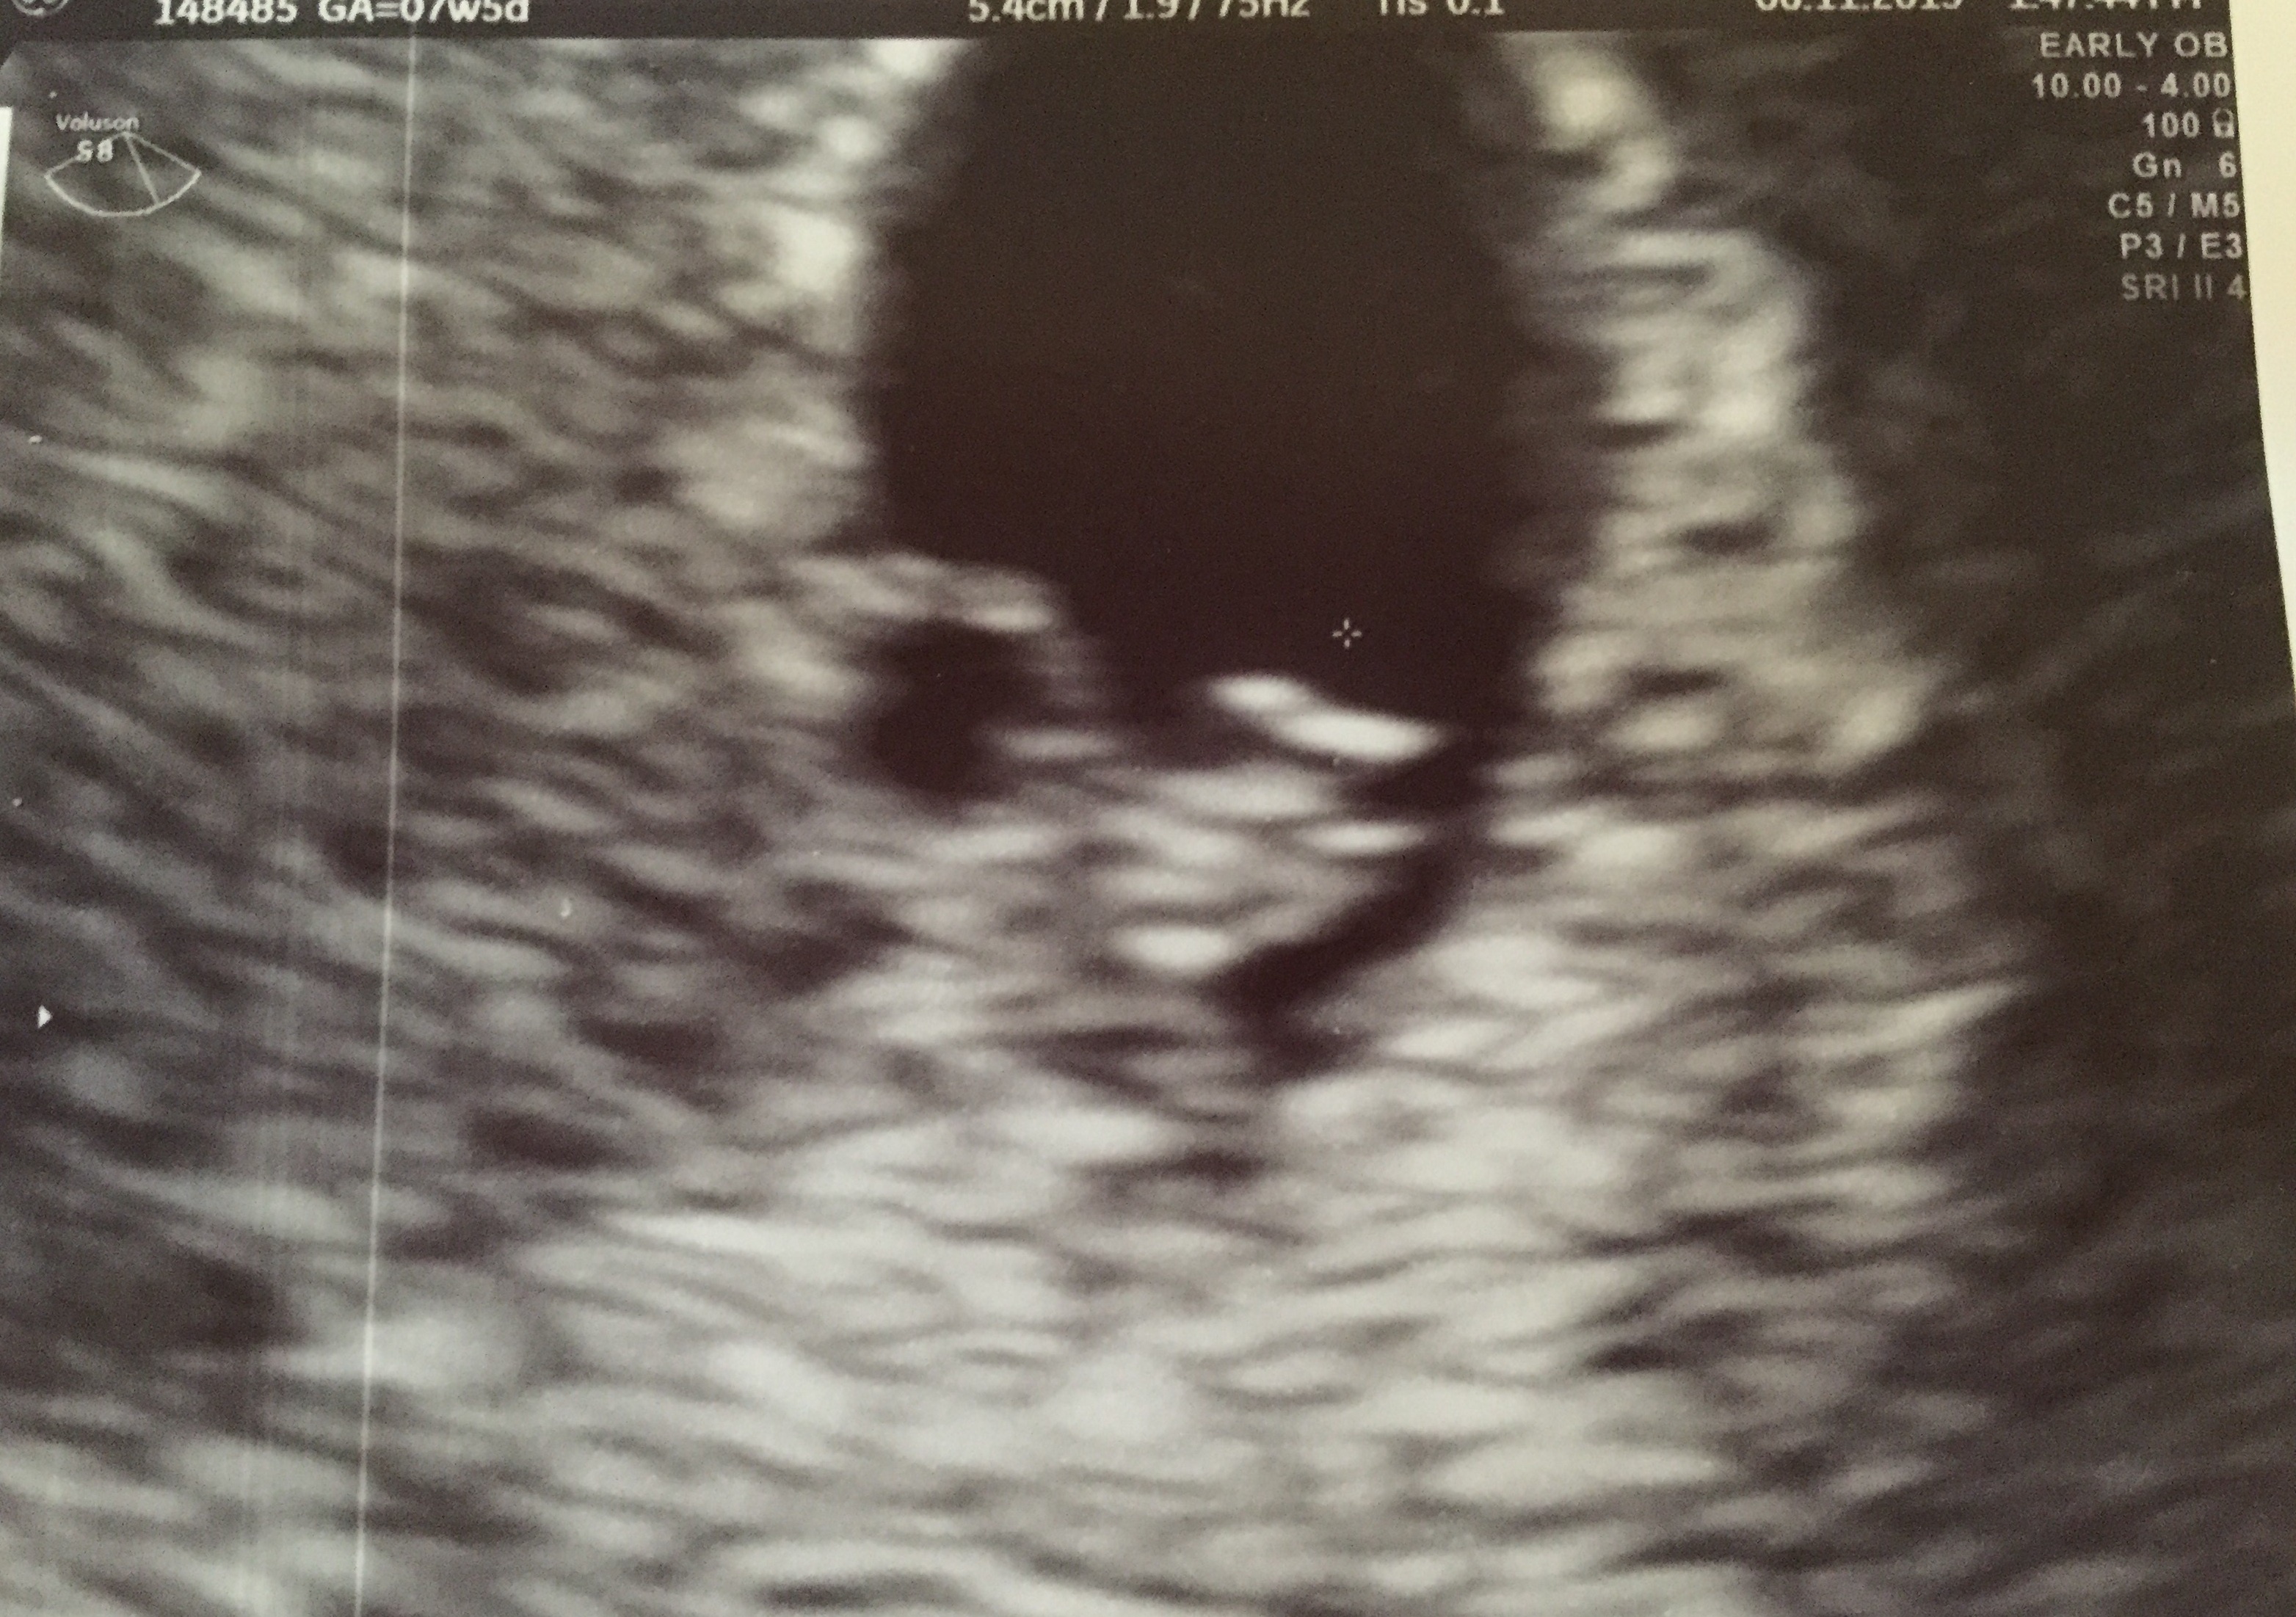

Here is our LO from our dating u/s yesterday (measuring 6w6d then, 7w today). It was so amazing & surreal to see its heart beating. I now fully understand "love at first sight." (So corny, I know lol)